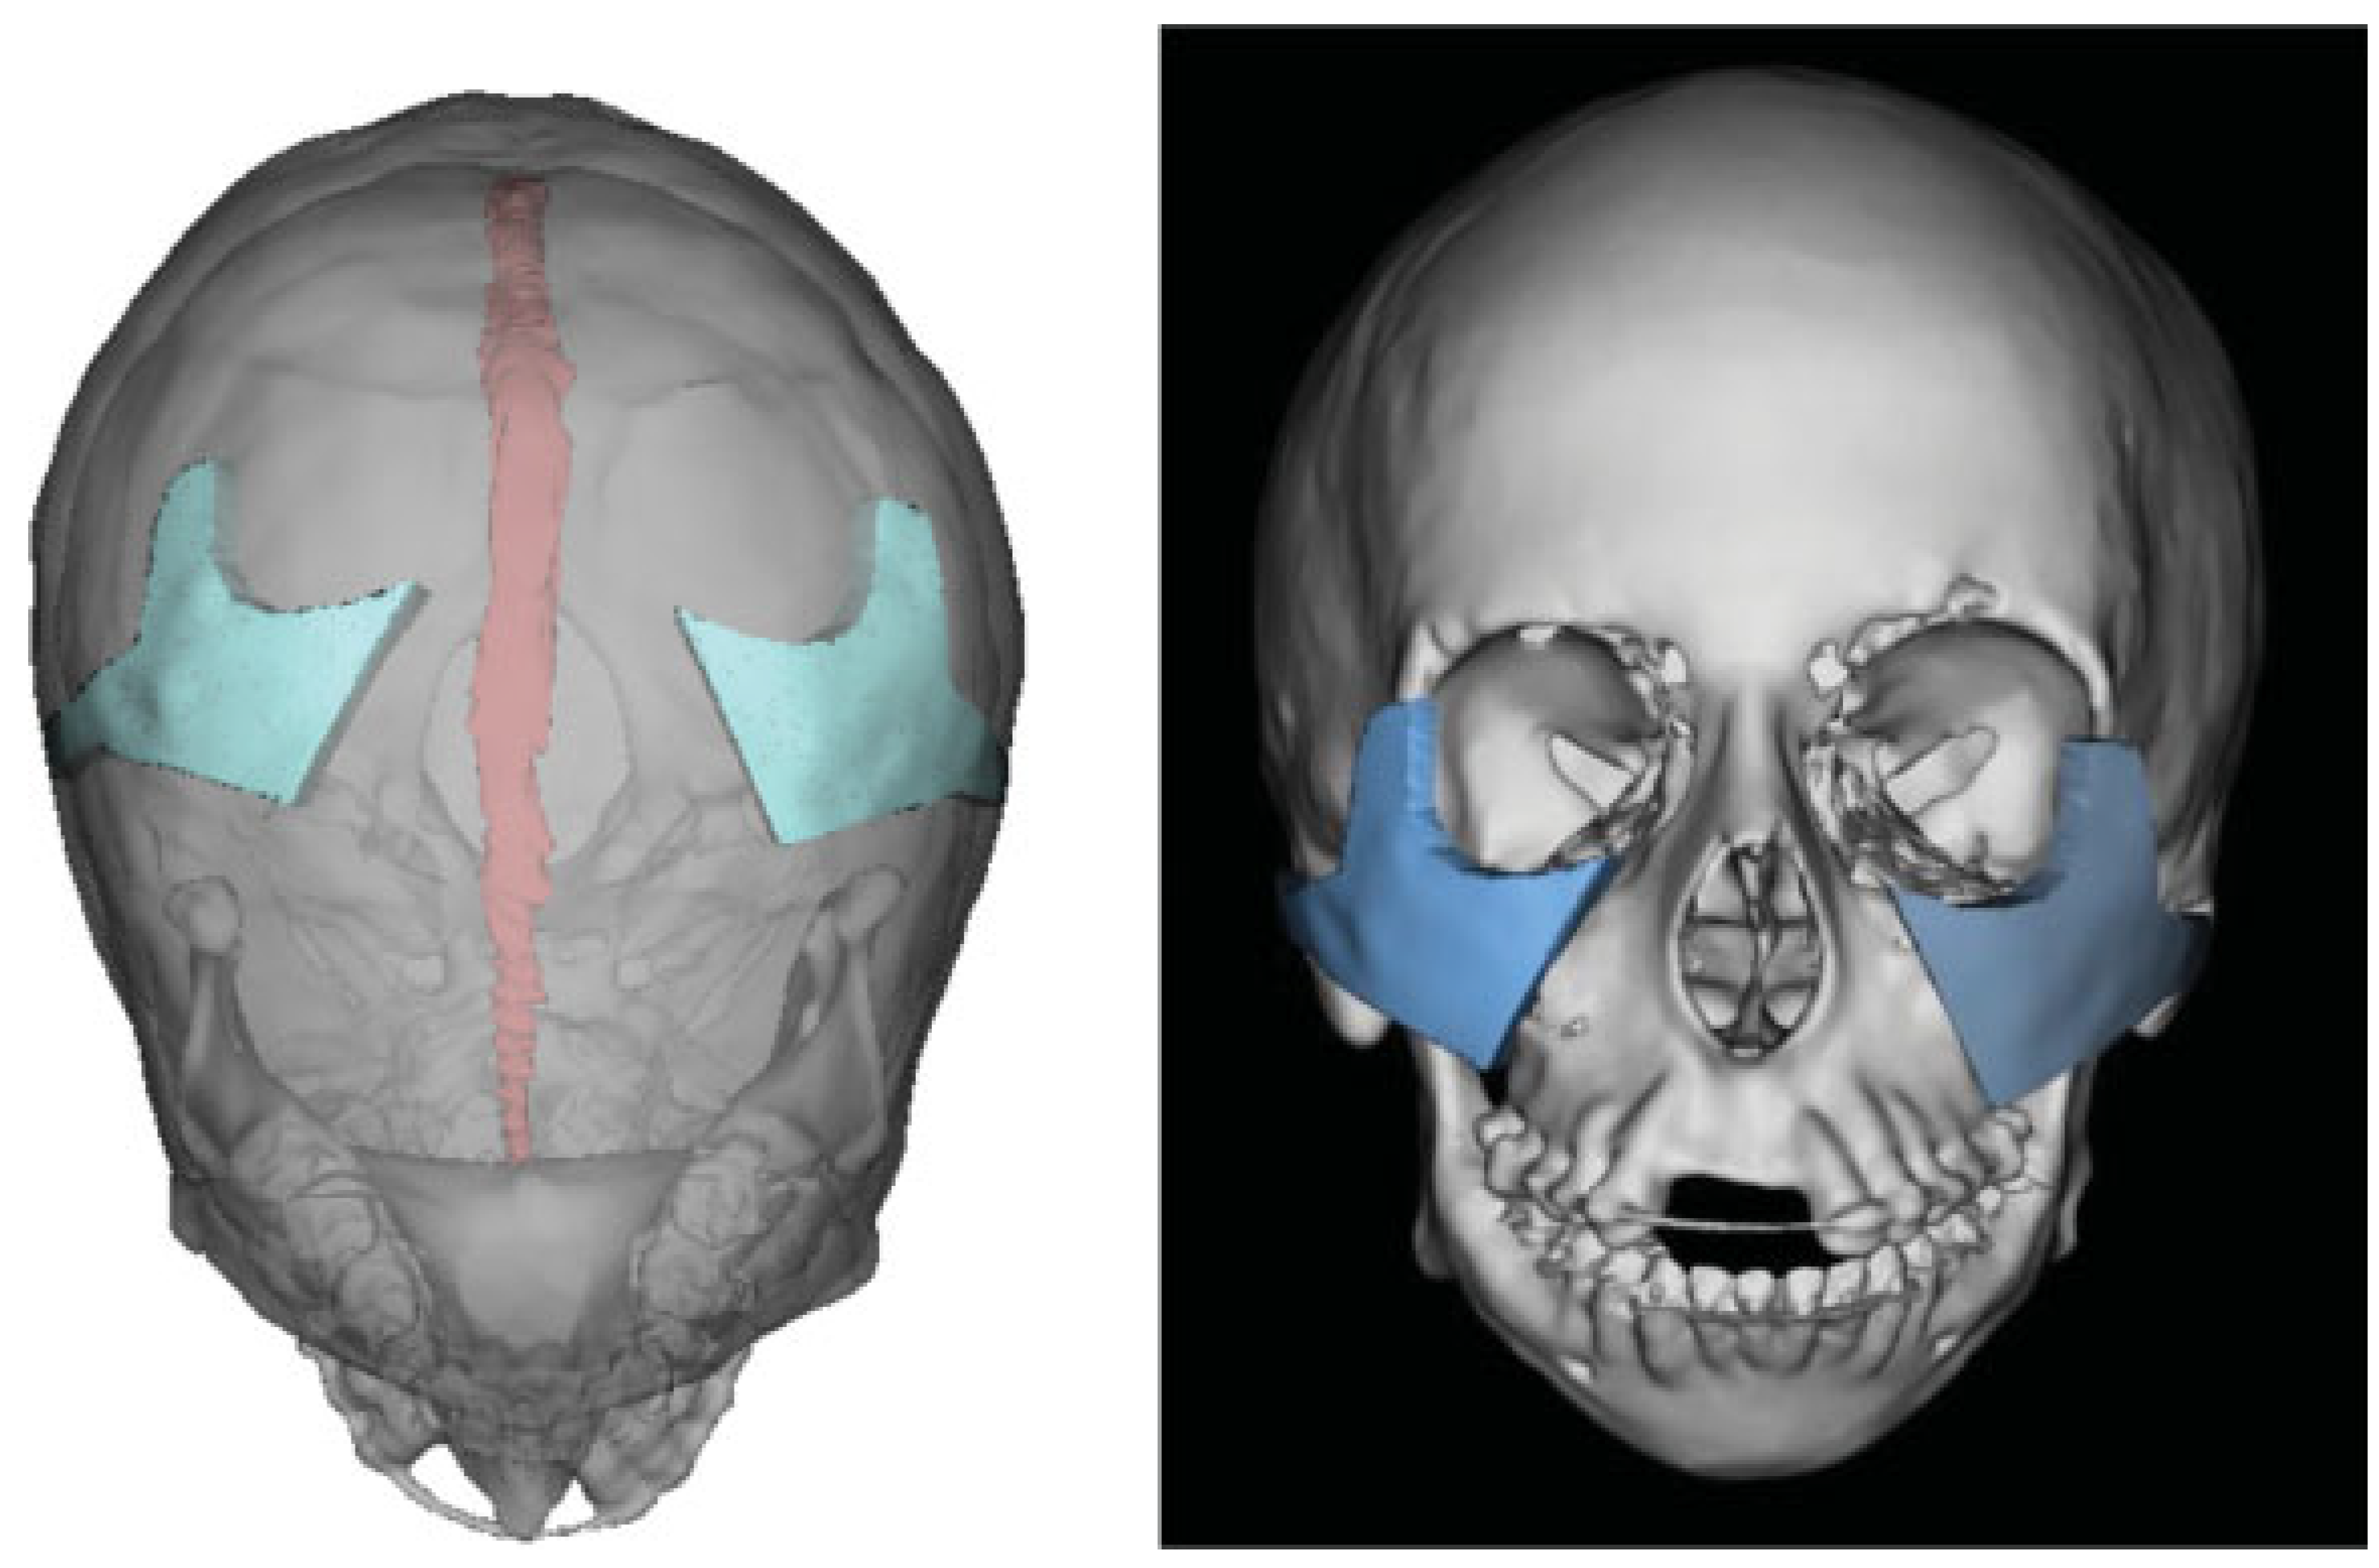

Given the extent of her mid- and lower facial hypoplasia, a multistage approach for surgical reconstruction was designed to augment her midface and to advance her retrognathic jaw position. The first stage focused on midface reconstruction. Her primary concern was midface hypoplasia and we wished to set the midface in projection prior to performing orthognathic surgery. Using VSP, we realized that a Le Fort II osteotomy would not have given sufficient bone stock for a subsequent bilateral split sagittal osteotomy. We thus elected to use full-thickness autologous calvarial bone as an onlay augmentation. Computed tomography (CT) of the face and brain with 1-mm-thin cuts and 3D reconstruction were performed. The imaging data were then submitted (3D Systems; Rock Hill, SC) for VSP. The location of calvarial bone graft harvest was selected based on the desired contour, shape, and optimal thickness of the final malar autologous implant (Figure 2). Cutting guides were designed to allow craniotomy to be performed in a safe location, away from the sagittal sinus. The craniotomy cutting guide was designed so that it would allow adequate amount of split-thickness calvarial bone graft to reconstruct the donor site (Figure 2).

Figure 2.

Computer-aided design and computer-aided manufacturing. Zygoma templates were designed based on normal anatomy. The templates were transposed to parietal bone, where ideal calvarial donor sites were chosen based on shape, contour, and thickness.